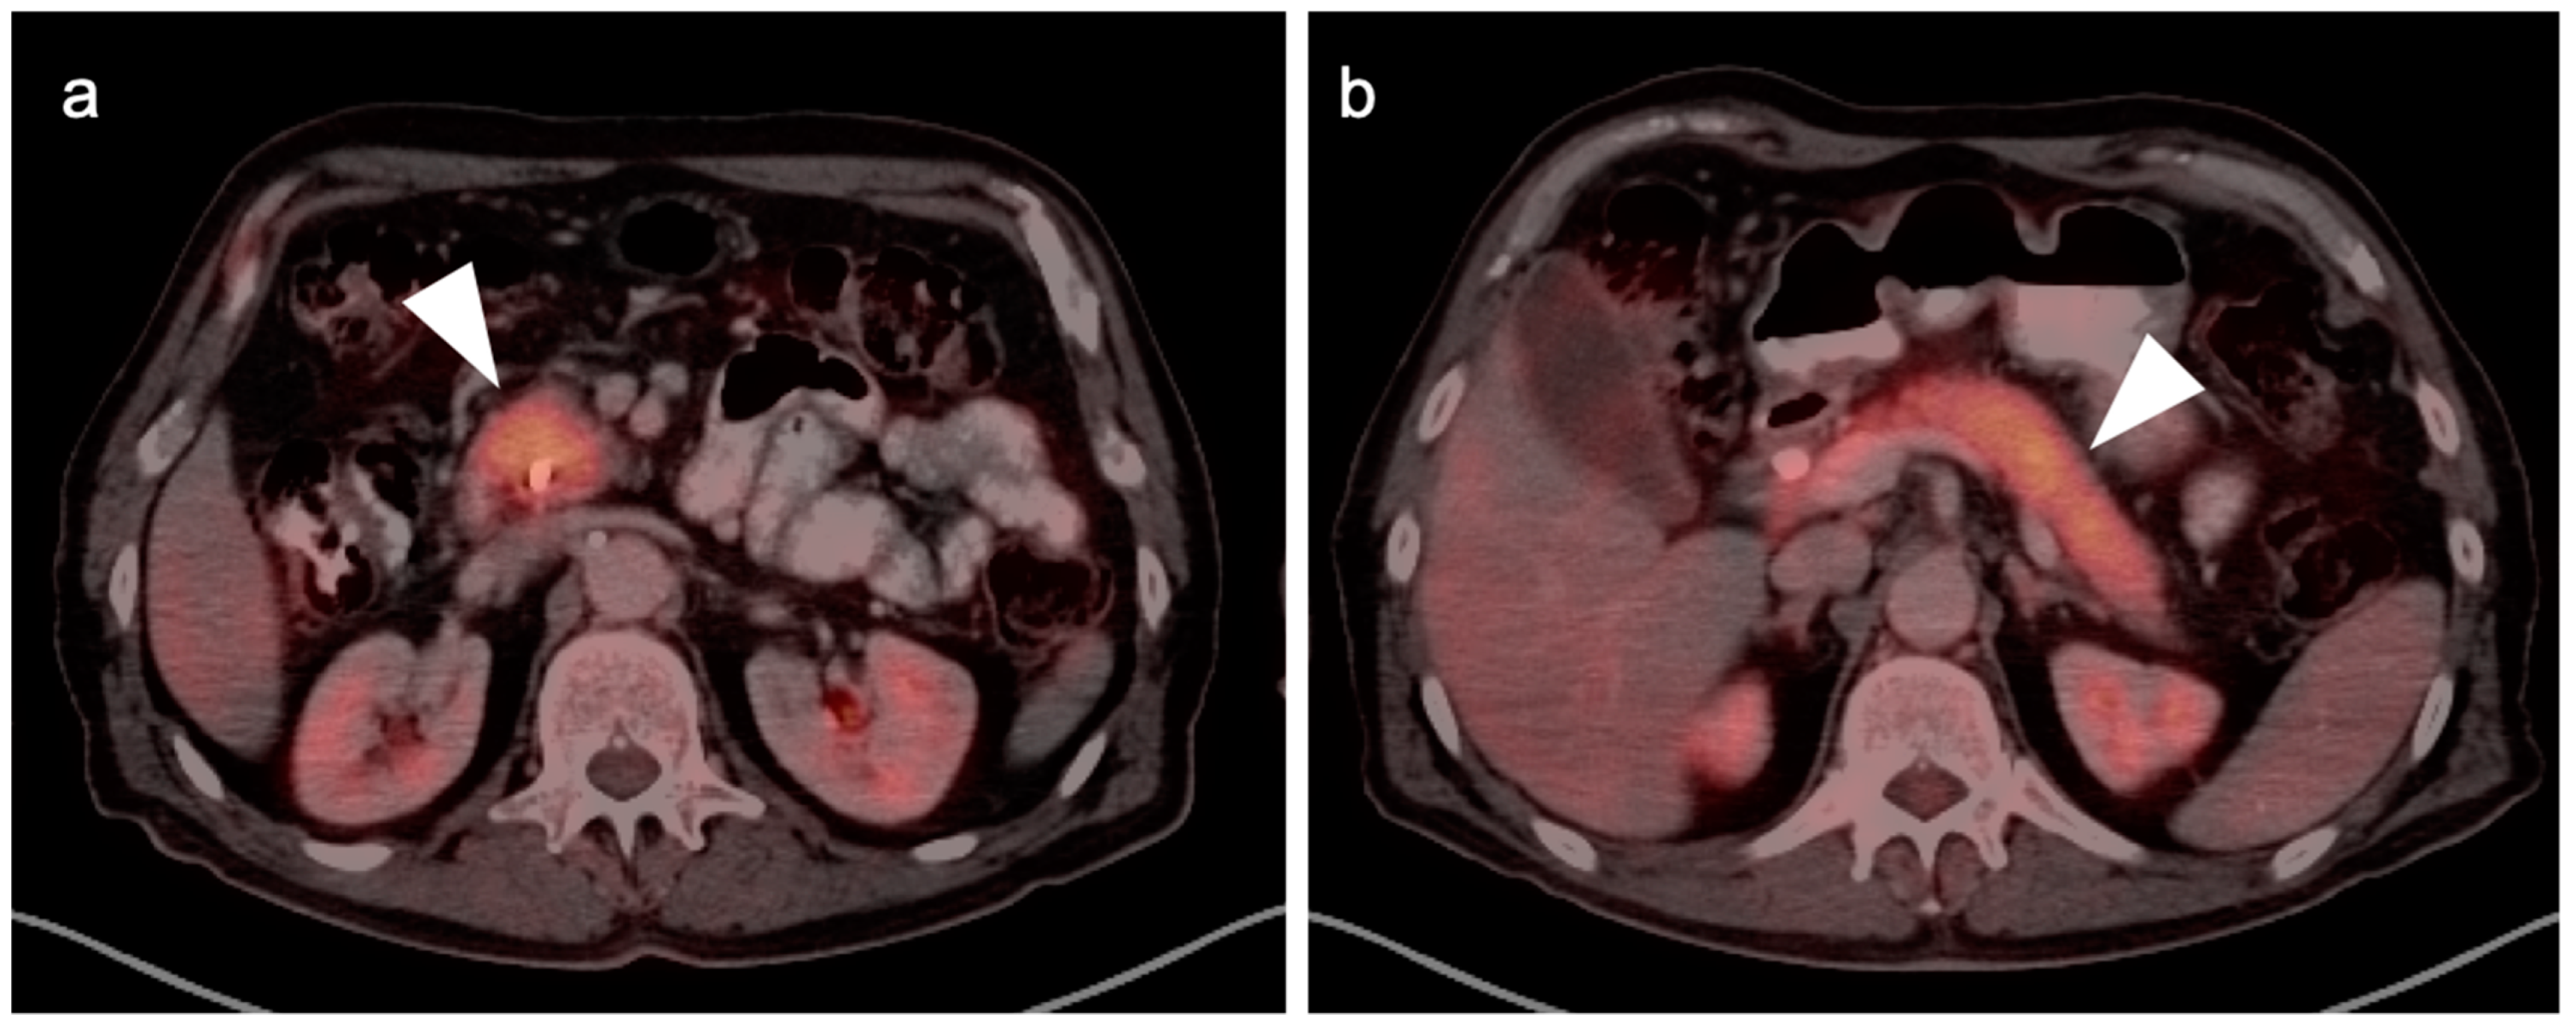

4. Hepatocellular Carcinoma